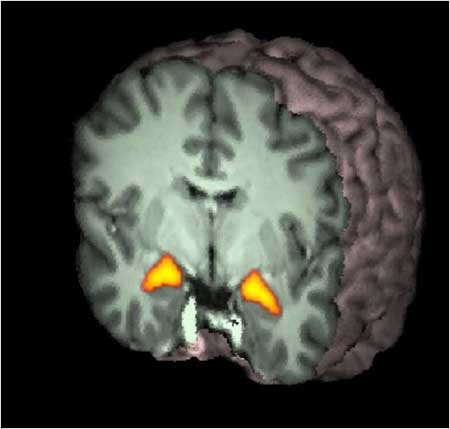

Among the ads that seem relatively successful, I want to single out the Michelob ad. Above is a picture showing the brain activation associated with the ad. What is interesting is the strong response - indicated by the arrow - in 'mirror neuron' areas, premotor areas active when you make an action and when you see somebody else making the same action. The activity in these areas may represent some form of empathic response. Or, given that these areas are also premotor areas for mouth movements, it may represent the simulated action of drinking a beer elicited in viewers by the ad. Whatever it is, it seems a good brain response to the ad.

Finally, the highlights of the day. This is the brain activity of one of our subjects recorded while the subject was watching the Disney ad. Both mirror neuron areas and ventral striatum - indicated by the yellow arrows - are engaged by the ad.

Mirror neuron activity in the right posterior inferior frontal gyrus - indicating identification and empathy - while watching the Disney/NFL ad.

Ventral striatum activity - indicating reward processing - while watching the Disney/NFL ad.